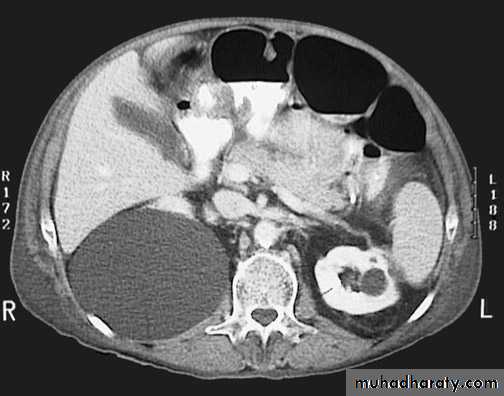

Congenital cystic kidney (polycystic kidney) (Adult cystic renal disease)

Autosomal dominant, transmitted by either parents, 50% of offspring affected.

Both kidneys replaced by large no. of cysts of variable size which make the kidney of large size.

The cysts contain clear fluid but sometimes blood.

The cysts progressively increase in size causing pressure atrophy of the renal parenchyma and pressing the ureter.

15% associated with cystic disease of liver, lung, pancreas or spleen.

Clinical pictures:

Rarely gives clinical manifestation before 4o years

Asymptomatic: diagnosed accidentally.

Pain: due to pedicle stretching, stone, ureteric obstruction, bleeding inside cyst or infection.

Hematuria: cyst distention and rupture to the collecting system.

Infection: renal or cyst infection causes fever, rigor and loin pain.

Hypertension: in 70%, Unknown cause.

Renal impairment: anorexia, headache, nausea, vomiting, drowsiness and coma.

Renal enlargement: large knobby palpable kidney

Diagnosis: Family history of polycystic disease.

U/S, IVU, CT scan, MRI